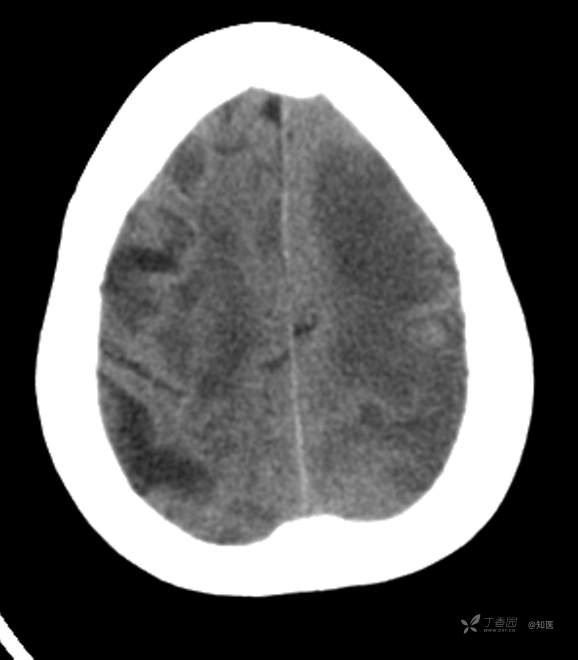

4-22日查房患者呈昏睡状,混合性失语,右侧肢体肌力障碍较入院时加重,胃肠减压引流物为深黄绿色液体,量约150ml。查体:GCS 9分(睁眼反应 3分+语言 1分+运动 5分),NHISS评分23分(意识水平 2分+提问 2分+指令 1分+凝视 2分+面瘫2+左上肢 1分+右上肢4分+左下肢 2分+右下肢4分+语言 3分),昏睡状,查体欠合作,混合性失语,粗测智能查体不配合。双眼闭目紧,双侧球结膜水肿,双侧瞳孔等大等圆,直径约4.0mm,对光反射灵敏,眼球无自主运动,无眼震,右侧鼻唇沟浅,口角向左歪斜。咽部查体不配合。转颈、耸肩查体不配合。伸舌不配合。右上肢肌力1级,右下肢肌力2级,左上肢肌力3级,左下肢肌力4级,四肢肌张力减低。四肢深浅感觉及共济运动查体不配合。右侧巴氏征阳性,左侧巴氏征阴性。颈抵抗。双侧布氏征及克氏征均阴性。辅助检查:头颅+胸部CT:与前片(2021-4-21 13:57)对比,现片示:1、环池、桥前池及大脑镰后部及小脑幕高密度影,考虑出血,较前新发。2、额颞顶叶高低混杂密度影,考虑梗塞伴造影剂残留;左侧大脑中动脉走行区致密影,系术后改变;请结合临床。3、多发腔梗,脑白质脱髓鞘,脑萎缩。4、双肺间质性改变,双肺下叶纤维索条,双侧胸腔微少量积液征象,双侧胸膜增厚。5、主动脉及冠状动脉管壁多发钙化斑块。三线主任医师、二线主治医师查房后示:根据患者病史、体征及辅助检查,目前诊断:1.脑梗死出血转化;2.左侧大脑中动脉次全闭塞;3.左侧大脑中动脉支架植入术后;4.高血压2级(很高危);5.2型糖尿病;6.应激性溃疡伴出血。目前病情及治疗上需注意以下问题:1.患者出血转化,增加脱水剂剂量,调整为20%甘露醇 125ml 每8小时一次、甘油果糖 250ml 每12小时一次,同时结合患者球结膜水肿,白蛋白正常低值,今日给予补充人血白蛋白10g,注意监测电解质等变化。2.患者为蛛网膜下腔出血,给予泵入尼莫地平预防脑血管痉挛。3.患者左侧大脑半球见大片脑白质脱髓鞘,考虑脑白质营养不良,给予维生素B1、维生素B12、维生素C、维生素B6及依达拉奉改善微血管通透性;4.患者出现应激性溃疡伴出血,今日暂禁食,给予泮托拉唑抑酸及肠外营养补充,密切观察消化道出血情况,根据病情变化调整抑酸药物剂量及频次;5.患者卧床,今晨见明显痰多,给予化痰等对症处理,监测血常规及脓毒症2项指标。6.向家属再次告知病情,因患者高龄、既往高血压及糖尿病病史,此次治疗出现出血转化,存在意识障碍加深、病情加重可能。7.密切观察神经系统体征变化。遵嘱执行。

4-23日查房:患者呈中度醒状昏迷,右侧肢体肌力障碍较入院时加重,胃肠减压引流物为黄绿色液体,量约200ml。入院后至今晨入量为4050ml,出量为4850ml。查体:GCS 6分(睁眼反应 2分+语言 1分+运动 3分),NHISS评分35分(意识水平 3分+提问 2分+指令 2分+面瘫3分+左上肢 4分+右上肢4分+左下肢 4分+右下肢4分+感觉 2分+语言 3分+构音障碍 2分+忽视 2分)。中度昏迷。双目睁眼状,双侧球结膜水肿较昨日明显,双侧瞳孔等圆,不等大,右侧直径约3.5mm,左侧瞳孔直径约3.0mm,对光反射灵敏,眼球无自主运动,无眼震。右侧鼻唇沟浅,口角向左歪斜。咽部查体不配合。转颈、耸肩查体不配合。伸舌不配合。四肢肌力检查不配合,右上肢落鞭征阳性,左上肢落鞭征阴性,右下肢不能撑于床面,左下肢可撑于床面,四肢肌张力减低。四肢深浅感觉及共济运动查体不配合。右侧巴氏征阳性,左侧巴氏征阴性。颈抵抗。双侧布氏征及克氏征均阴性。辅助检查:经颅多普勒示:左侧大脑中动脉峰值流速极低,右侧大脑中动脉及双侧大脑前动脉血流速度未见明显异常。头颅CT(2021-04-22):与前片(2021-4-21)对比,现片示:1.环池、桥前池及大脑镰后部及小脑幕高密度影,较前减少。2.额颞顶叶高低混杂密度影,考虑梗塞伴造影剂残留;左侧大脑中动脉走行区致密影,系术后改变;基本同前。请结合临床。3.多发腔梗,脑白质脱髓鞘,脑萎缩。同前。二线主治医师查房后示:患者目前诊断明确。现治疗上需注意以下问题:1.患者夜间体温上升,最高38度,结合患者卧床、痰多、不易咳出,且化验检查提示炎性指标较前明显升高,今日给予头孢哌酮舒巴坦抗感染治疗,同时继续雾化祛痰等。2.因患者应激性溃疡并出血,昨日查胃液潜血阳性,但经给予泮托拉唑抑酸护胃治疗后消化道出血未进行性加重,胃管引流物为黄绿色液体,今日暂继续给予氨基酸、脂肪乳等肠外营养支持,安排再次复查胃液潜血,若转阴可给予肠内营养加强支持治疗。3.患者血压仍有偏高,夜间泵入乌拉地尔控制,今日给予左氨氯地平平稳控制血压,监测血压变化。4.患者昨日血糖波动在6.8-11.4mmol/l,结合其糖化血红蛋白为6.4%,暂不干预血糖,继续监测血糖变化。5.患者意识障碍程度加重,双侧瞳孔不等大,但光反射灵敏,考虑与脑梗死后水肿高峰有关,治疗上继续加强脱水,向家属再次详细告知病情及目前诊疗方案,存在颅内压增高至脑疝形成、呼吸心跳骤停可能,表示理解知情。密切观察生命体征及神经系统体征变化。遵嘱执行。